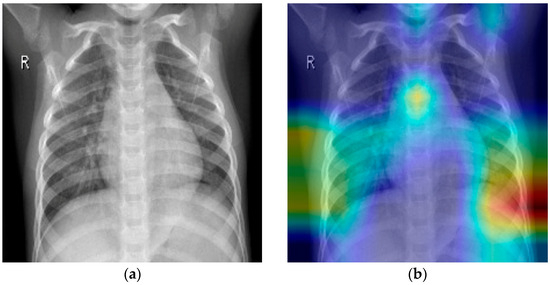

4. MobileNet Architecture

3.1. Data Overview

3.2. EDA and Preprocessing